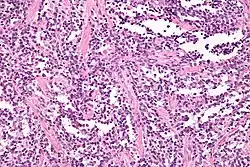

![]() Obraz histologiczny mięsaka prążkowanokomórkowego |